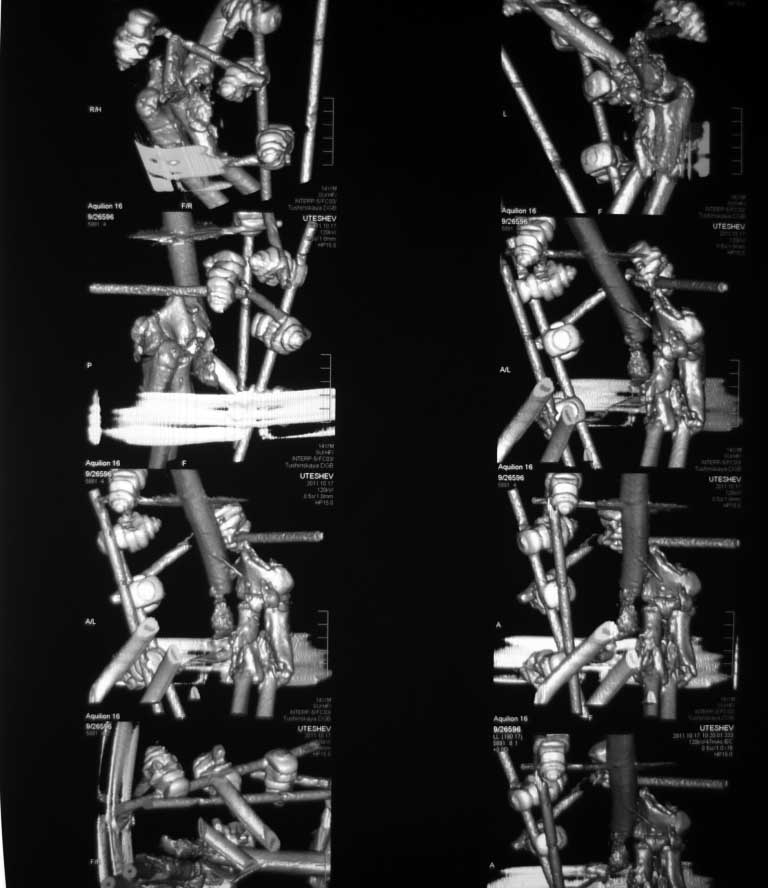

Выкладываю изображения.

План лечения: открытая репозиция. Собрать суставные фрагмент. Фиксация: спицы, кан.шурупы, реконструктивные пластины, АВФ с локтевым шарниром. Бусы с ванкомицином. Дренирование, вакууимирование.

КТ - вот это другое дело!

естествено - репозиция отломков плеча, однако, не заморачивайтесь с суставом...